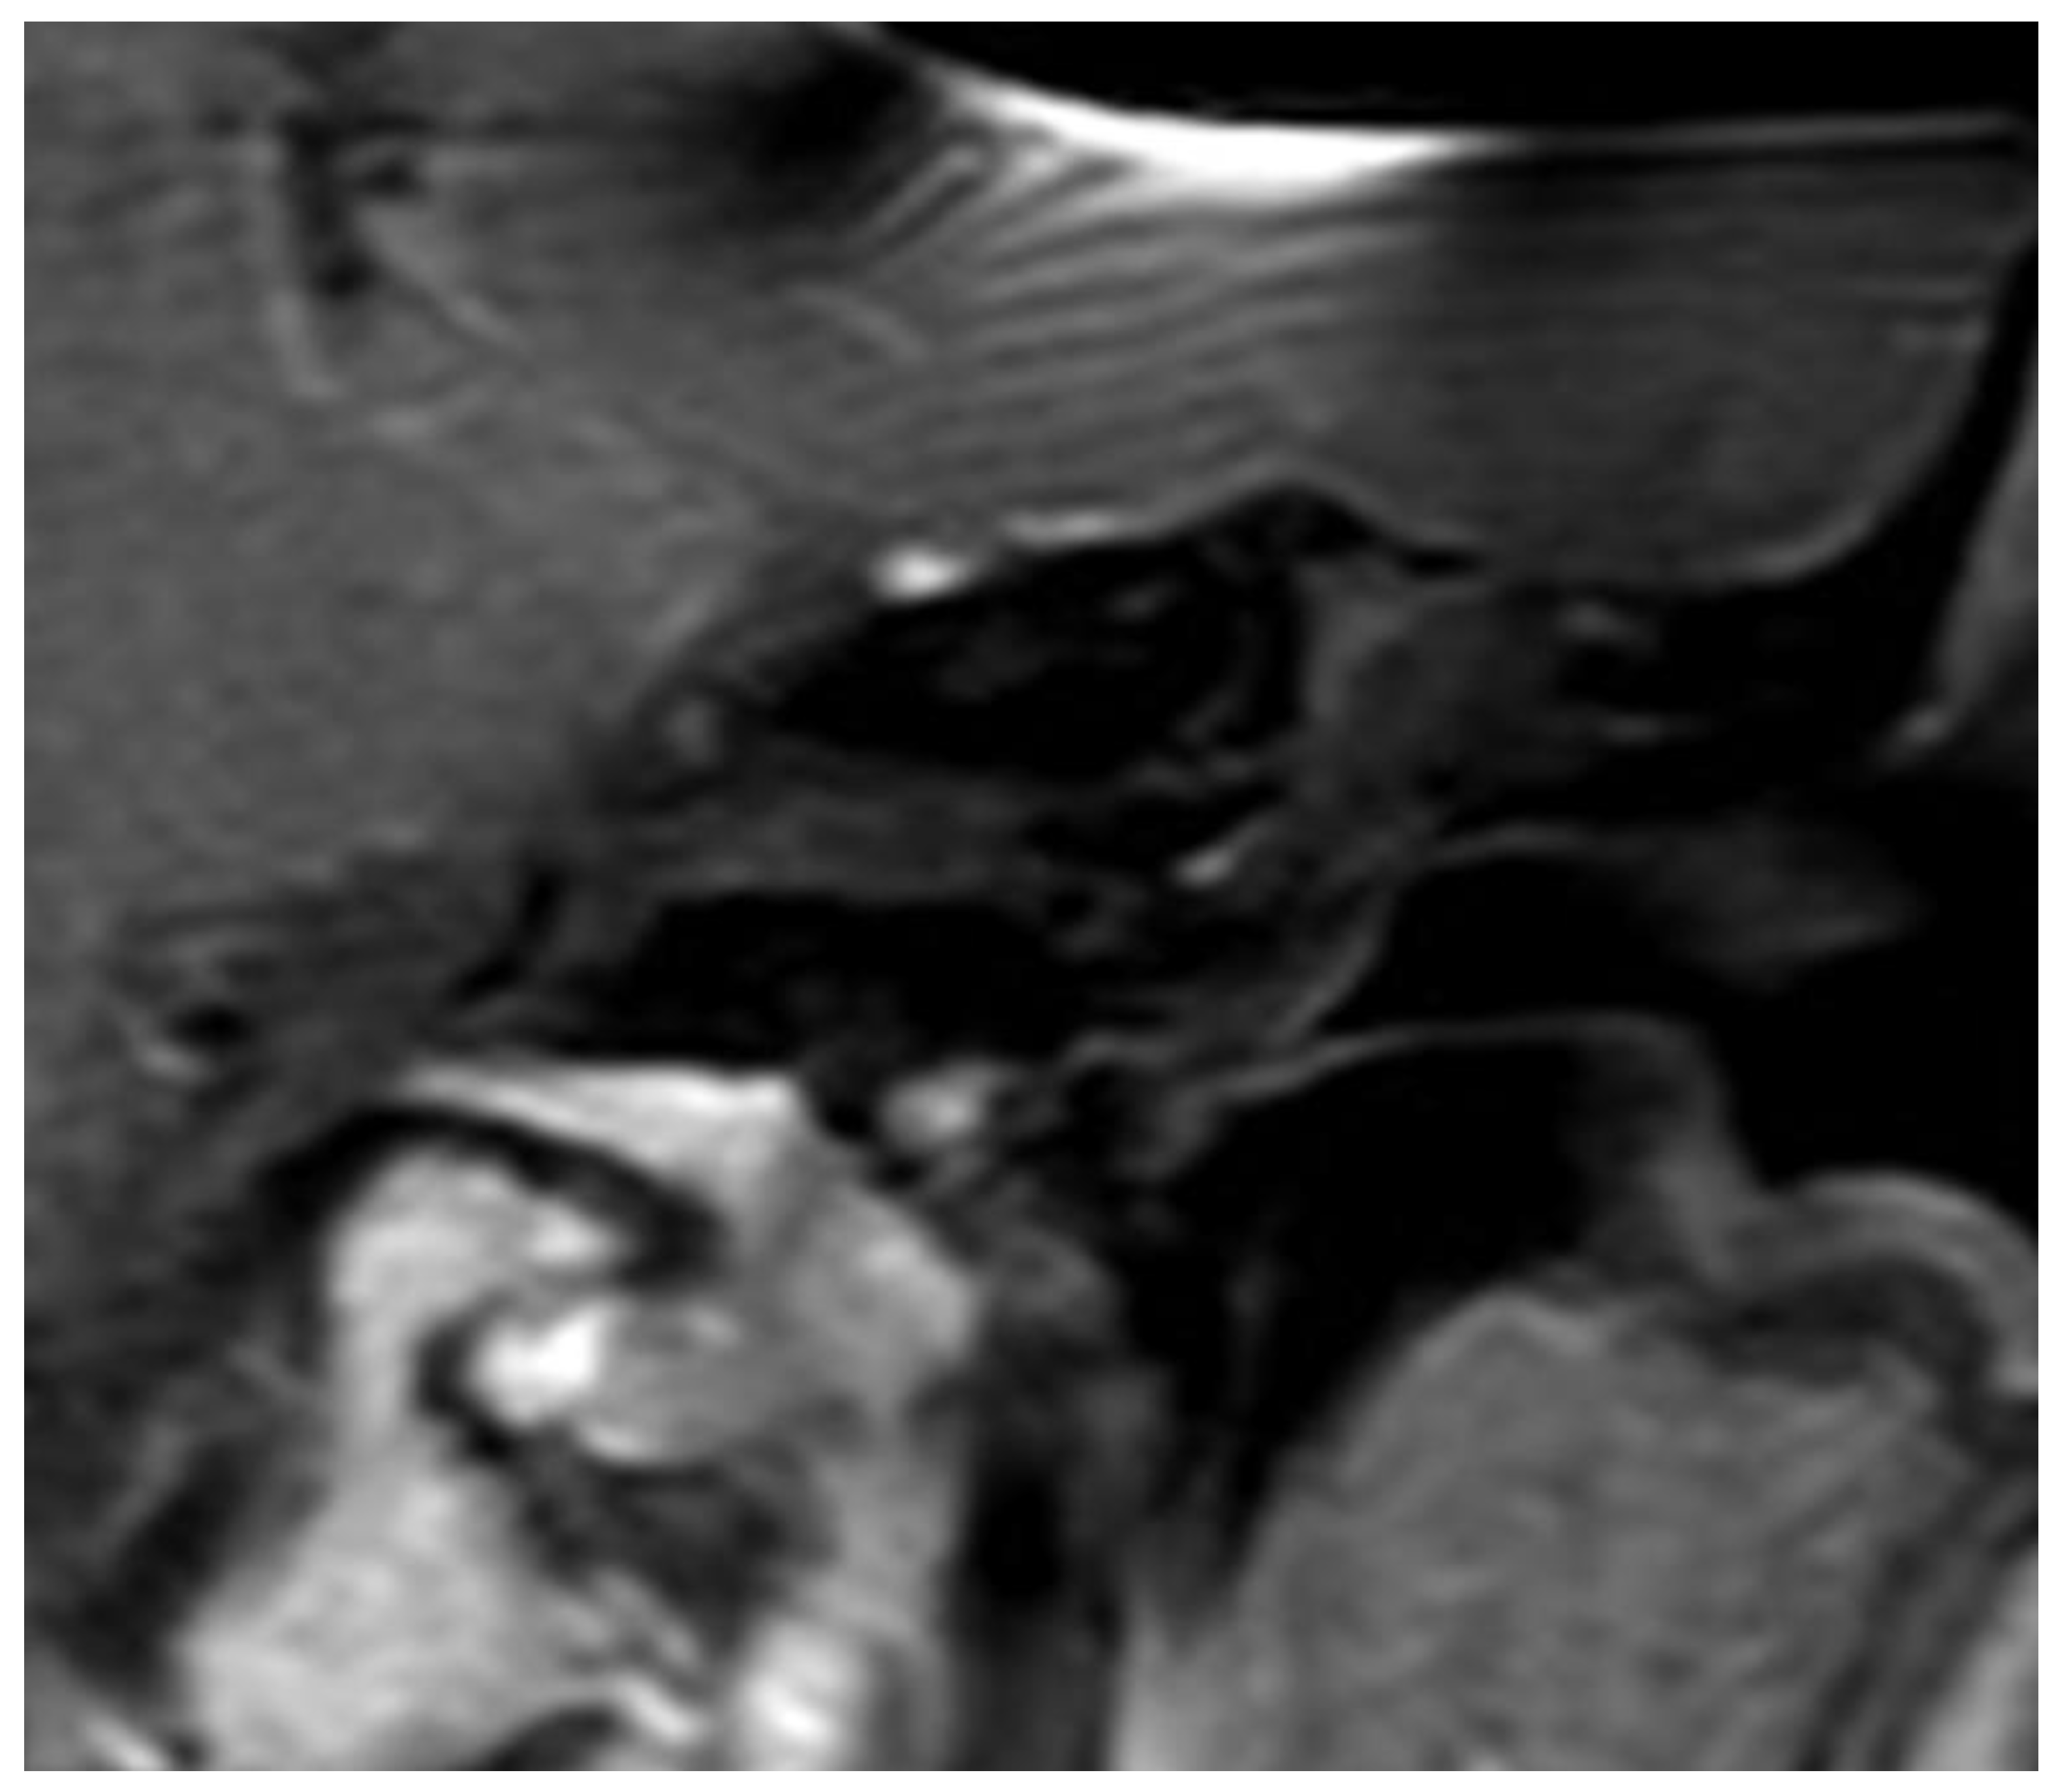

After the removal of parts of the tumor through the enlarged cochleostomy (Figure 1) the TRD was introduced (Figure 2) until the tip was visualized (Figure 3) and carefully grabbed out of the second turn access. By grabbing the tip, the device slipped into the cochleostomy and pushed parts of the tumor out of the second turn. Residual tumor parts could be detached by pipe cleaner handling (Figure 4) and sucked out (Figure 5).

The whole procedure lasted 15 minutes in each case. Comparing pre-OP (Figure 6) and post-OP (Figure 7) MRI scanning confirmed a complete removal of the tumor.

Figure 6. a, b: Pre-OP MRI.

Preprints 103791 g006

Figure 7. a, b: Post-OP MRI.

Preprints 103791 g007